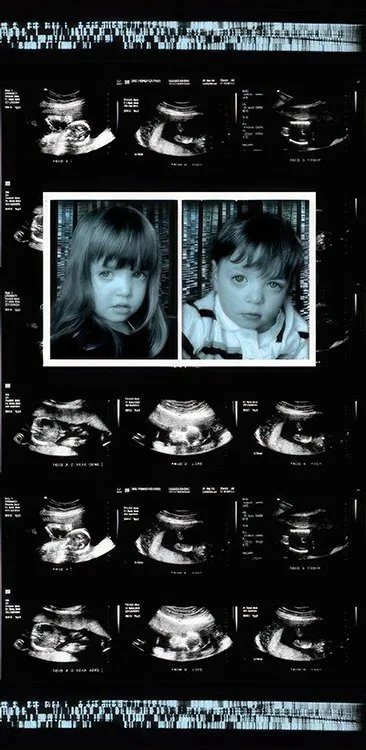

Comprising eight 47” x 23” backlit Plexiglas panels, each work features a portrait, often of individuals from diverse racial, ethnic, and cultural backgrounds. Surrounding these portraits are embedded CT scans, MRIs, and DNA sequencing gels. These medical images, reimagined as expressive symbols, evoke biological inheritance, invisible histories, and interior experience rather than clinical diagnosis.

Used metaphorically, DNA strands suggest ancestral continuity; CT scans and MRIs hint at the unknowable workings of body and psyche; ghostly anatomical forms recall trauma, resilience, and emotional scars. By pairing portraiture with interior imaging, the series questions how we perceive identity. Are we defined by surface appearance—skin, gender, dress—or by memory, genetics, and lived medical experience? Can scientific data be truly neutral, or does it reflect cultural bias and interpretation?

Twin 47” x 23”47” x 23”